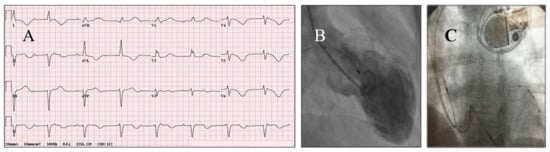

3.8. Thrombus and Prevention of Embolism in Patients with TTS